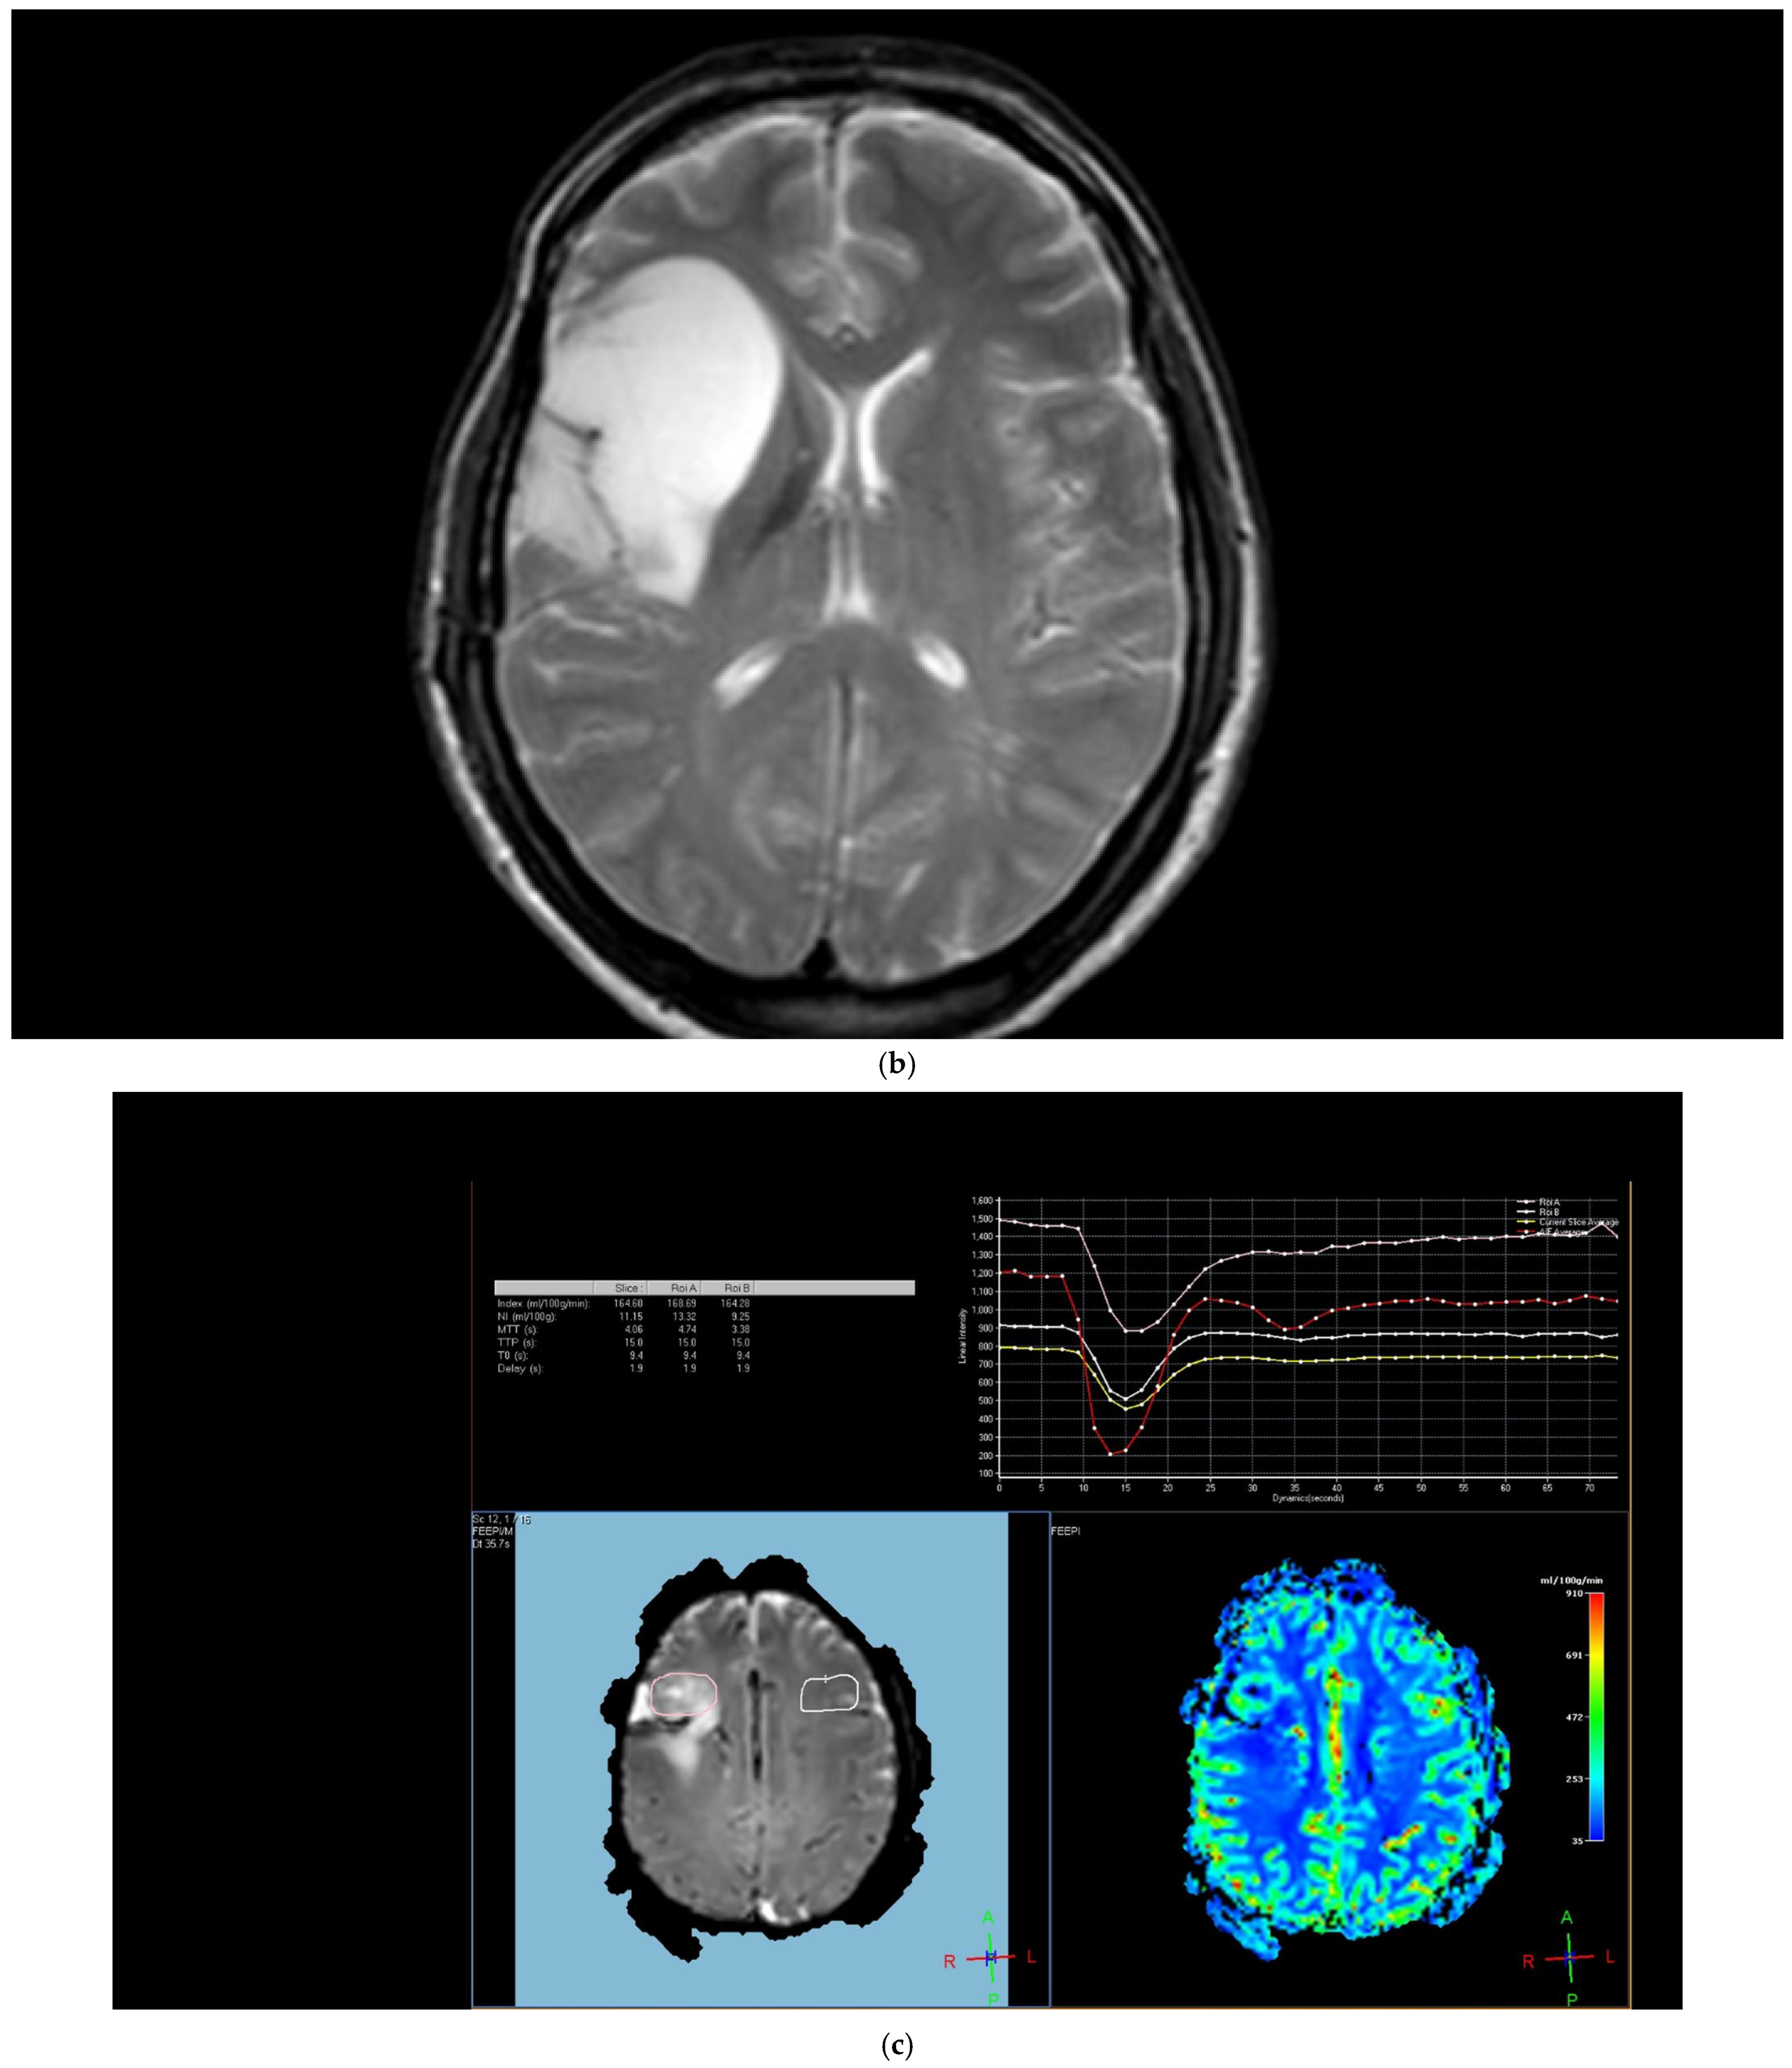

Figure 1. Brain magnetic resonance imaging (MRI) of a 52-year-old male with a low-grade glial tumor revealed (a) increased signal on a T2-weighted image, (b) hypoperfusion with a rCBV of 1.08 in perfusion-weighted imaging, Pink ROI is from tumor and white ROI is from contralateral parenchyma. and (c) a total of four ROIs—one from the peritumoral region (in blue), one from the contrast-enhancing tumoral area (in pink), and two from the contralateral tumor-free white matter areas corresponding to these regions (in white and red) in perfusion-weighted imaging.

The region of interest (ROI) size ranged from 2 to 10 square millimeters in area, depending on the size of the tumor. rCBV values were obtained by identifying regions of maximal perfusion from color maps (Figure 1). While measuring the rCBV values, care was taken to avoid any vascular structures, cerebrospinal fluid, or areas with high susceptibility. For the appropriate placement of the ROI, the rCBV maps were coregistered with FLAIR/T2-weighted, post-contrast T1-weighted, or SWI/GRE images. For multiple metastatic lesions, the measurements were performed from the largest and most enhanced tumoral lesion.

The rCBV values within the tumor and the surrounding area of edema were calculated using the following equation: rCBV = CBV tumoral or peritumoral edema/CBV of the corresponding locations at the uninvolved contralateral brain parenchyma. Perfusion curves were obtained for each lesion. All measurements were performed by the same neuroradiologist (AEP) blinded to the histological diagnosis of the tumors.